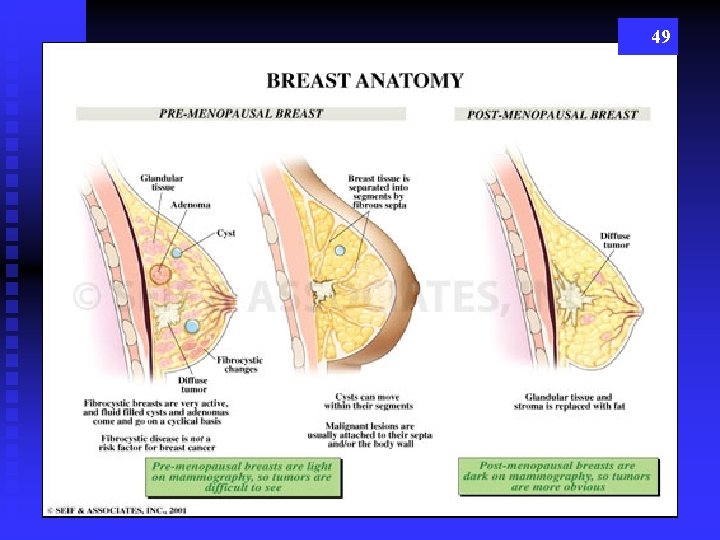

48

49

Breast Classifications Breast Changes with Age 50